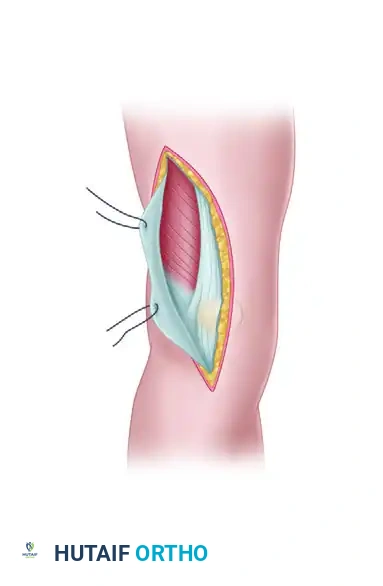

- Incision and Fascial Dissection: A midline or slightly lateral anterior longitudinal incision is made. The fascia overlying the quadriceps is incised longitudinally and lifted laterally off the underlying muscle belly.

FIGURE 54-74 A: Swashbuckler technique. The fascia overlying the quadriceps is incised longitudinally and lifted laterally off the underlying muscle.

- Arthrotomy: Farther laterally, the fascia over the quadriceps becomes confluent with the iliotibial band. A lateral parapatellar arthrotomy is performed. Proximally, the arthrotomy incision is carefully developed between the vastus lateralis muscle and the lateral retinaculum of the knee.

FIGURE 54-74 B: Swashbuckler technique. The lateral parapatellar arthrotomy is performed, separating the vastus lateralis from the lateral retinaculum.

- Proximal Release and Eversion: Proximal release of the vastus lateralis fibers from the lateral intermuscular septum allows for further mobilization of the quadriceps mechanism. The patella is everted medially, exposing the entire distal femur.